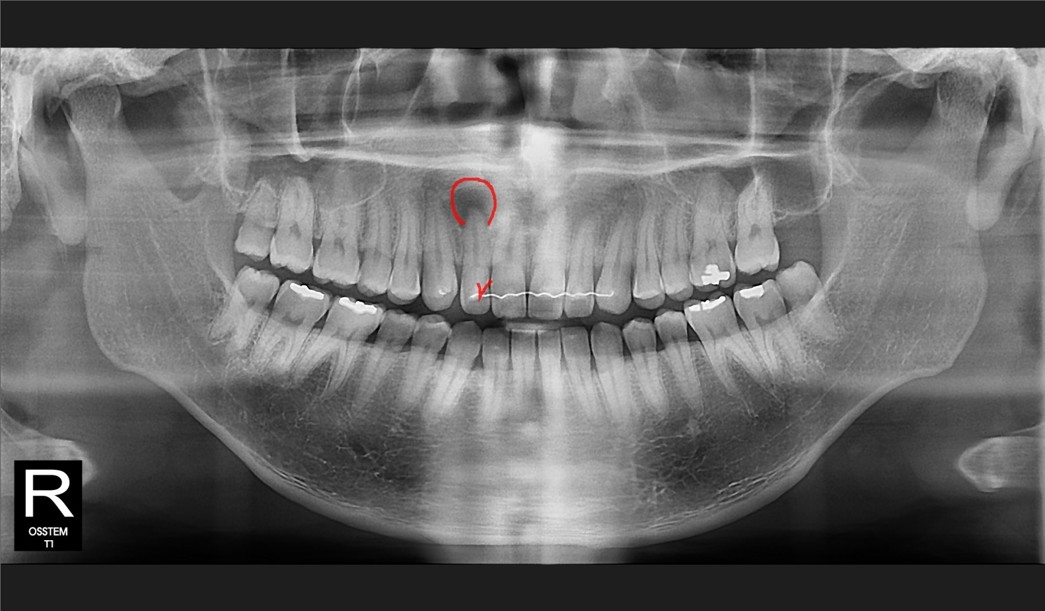

시간이 흐르고,

2025년 12월 환자분께서

다시 내원하셨습니다.

결과는 매우 긍정적이었습니다.

고름주머니는 거의 사라졌고

증상도 완전히 소실되었으며

크라운 마진도

아주 안정적이었습니다.

즉,

앞니 발치가

필요 없었던 케이스 였습니다.